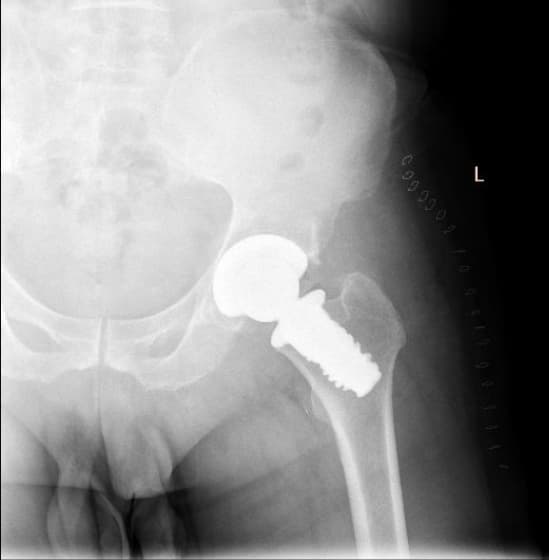

Түнхний үений төрөлхийн дутуу хөгжил

Нярай болон бага насны хүүхдийн хувьд түнхний үе төрөлхийн дутуу хөгжилтэй байх болон түнхний үений мултралттай тохиолдлууд байдаг. Нас биенд хүрсний дараа түнхний үений төрөлхийн өөрчлөлт нь артрит үүсгэх гол шалтгаан болдог бөгөөд хоёр хөл урт богино болж, аарцаг ясны тэгш хэм алдагдах болон түнхний үе мөн зэргэлдээх булчингын өвдөлт зовиур ихтэй болсноор хөдөлмөрийн чадвар муудаж, түүнчлэн тухайн хүний гоо зүй алдагдна. Иймээс түнхний үе солих мэс заслыг амьдралын чанарыг дээшлүүлэх, өвдөлт зовиур багасгах, хөлийн урт богиныг тэнцүүлж улмаар аарцаг ясны тэгш хэмийг хадгалах гоо сайхны зорилгоор хийж байна.

Түнхний үе солих мэс засал гэж юу вэ image15

Мэс заслын өмнөх болон дараах рентген зураг

Түнхний үе солих мэс засал гэж юу вэ image16Түнхний үе солих мэс засал гэж юу вэ image17